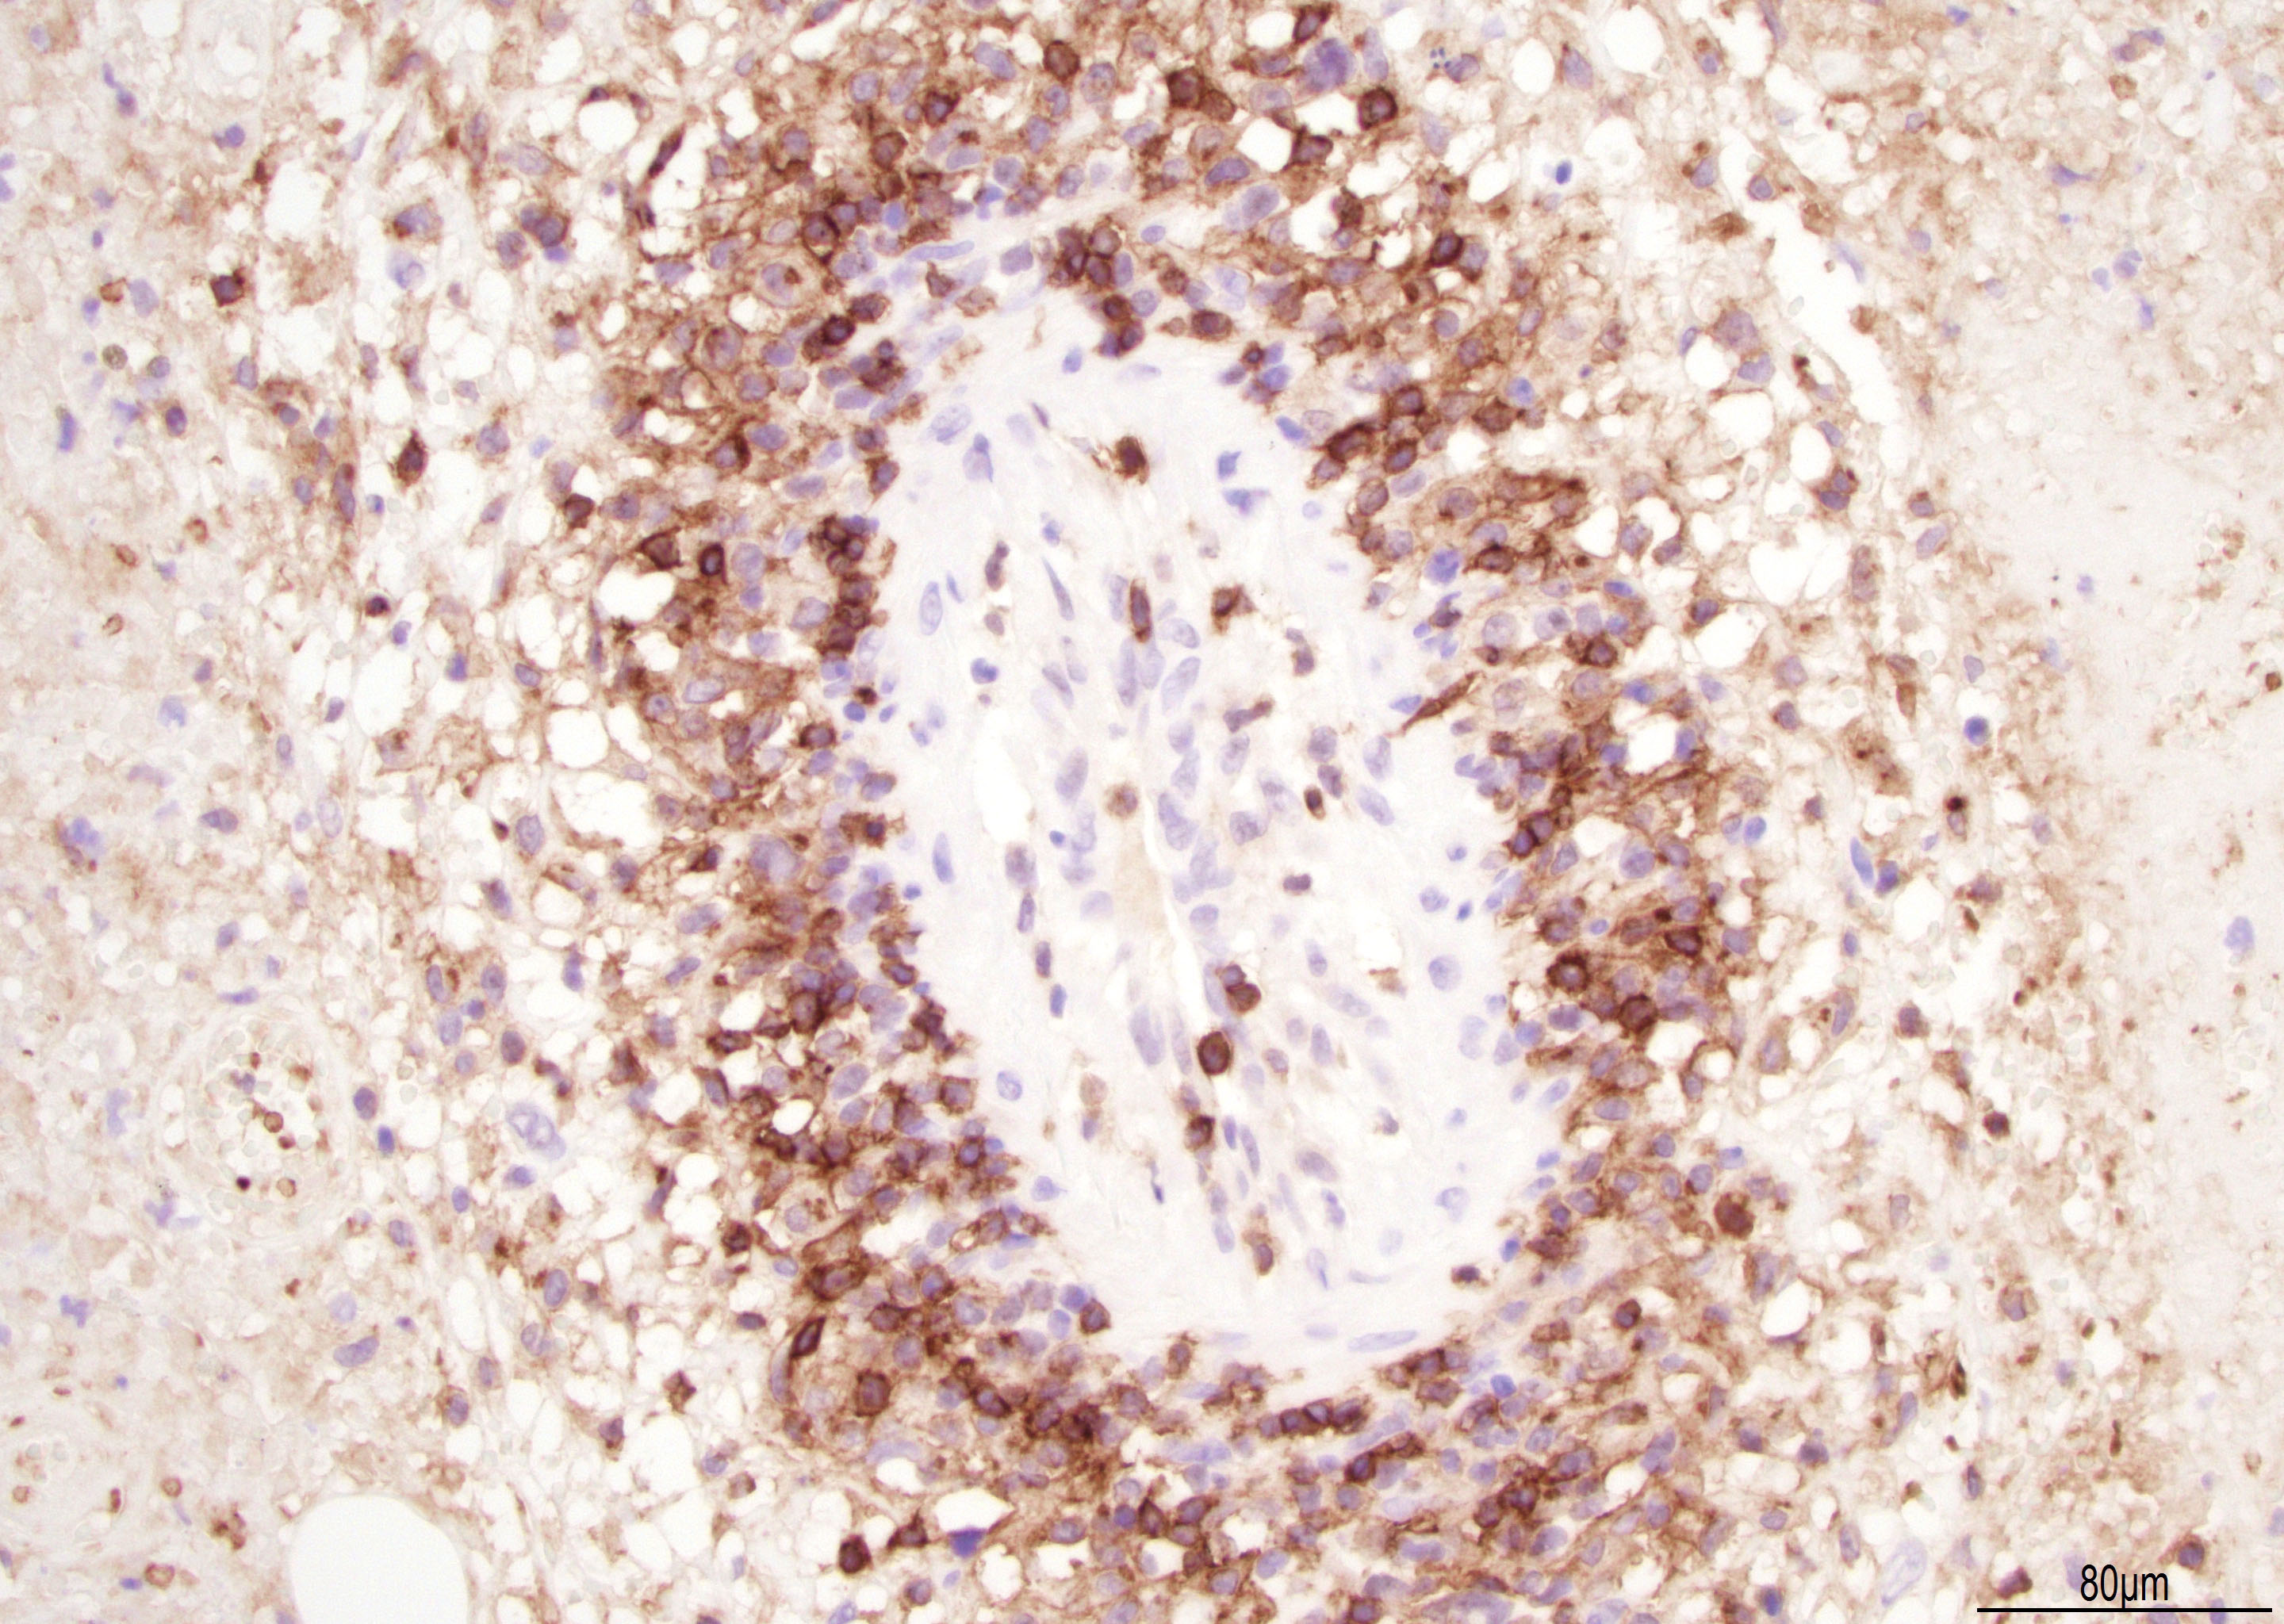

Microscopic (histologic) description

- Lymphomatoid papulosis is characterized by a wedge shaped pattern, with a wide superficial base and the tip at the bottom, usually deep dermis and less frequently into the subcutaneous tissue

- The most characteristic appearance is the presence of few to numerous large cells with a Hodgkin or Hodgkin-Reed Sternberg admixed with a reactive background of small lymphocytes and less frequently eosinophils, plasma cells and histiocytes

- The microscopic appearance and immunophenotype of large cells is variable and led to subclassification of lymphomatoid papulosis into different categories (J Am Acad Dermatol 2016;74:59, Blood 2019;133:1703, Semin Diagn Pathol 2017;34:22, J Am Acad Dermatol 2013;68:809, J Am Acad Dermatol 2012;66:928, Am J Clin Pathol 2003;119:731, Am J Surg Pathol 2010;34:1168, Am J Surg Pathol 2013;37:1)

- Type A: wedge shaped and extensive lymphoid infiltrate with neutrophils, eosinophils and histiocytes; CD30+ cells are scattered and the overall histologic appearance mimics classic Hodgkin lymphoma

Microscopic (histologic) images

Contributed by Roberto N. Miranda, M.D.

Positive stains

- Activate T helper phenotype (Semin Diagn Pathol 2017;34:22)